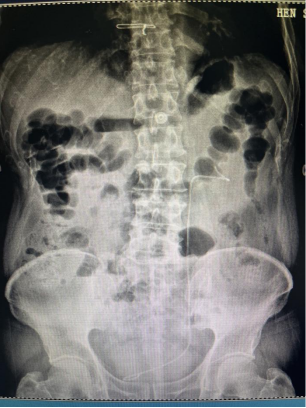

术后复查泌尿系平片显示无结石残留、支架管位置正常